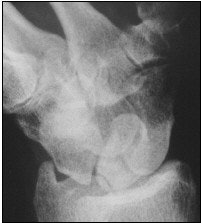

![]() |

| Panoramic radiograph (above) shows fracture line (arrow, fracture type A2). Berná J, Chavarria G, Albaladejo F, Meseguer L, Pellicer A, Sánchez-Cañizares, M, Pérez-Flores, D, "Panoramic Versus Conventional Radiography of Scaphoid Fractures," (AJR, January 2004, Vol.182, pp.155-159) |